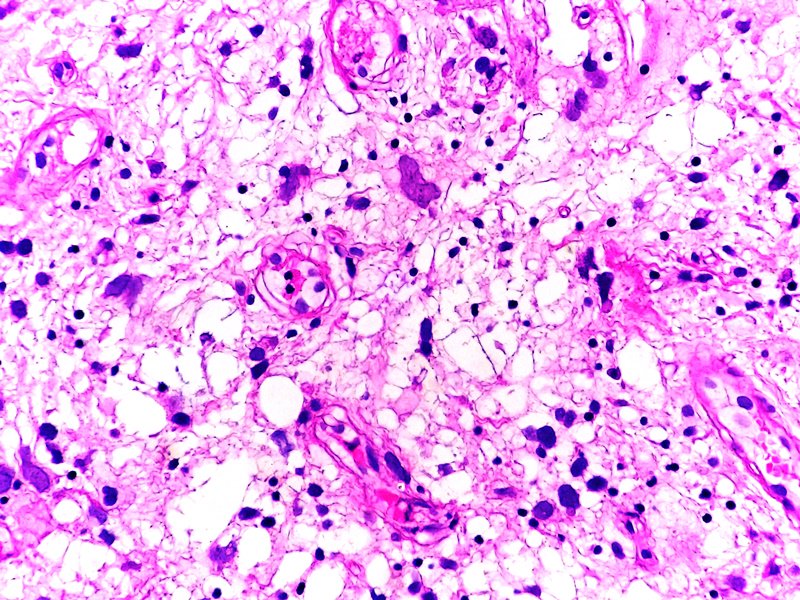

Anapat@Anapat_Lab·

Anapat tweet mediaAnapat tweet media